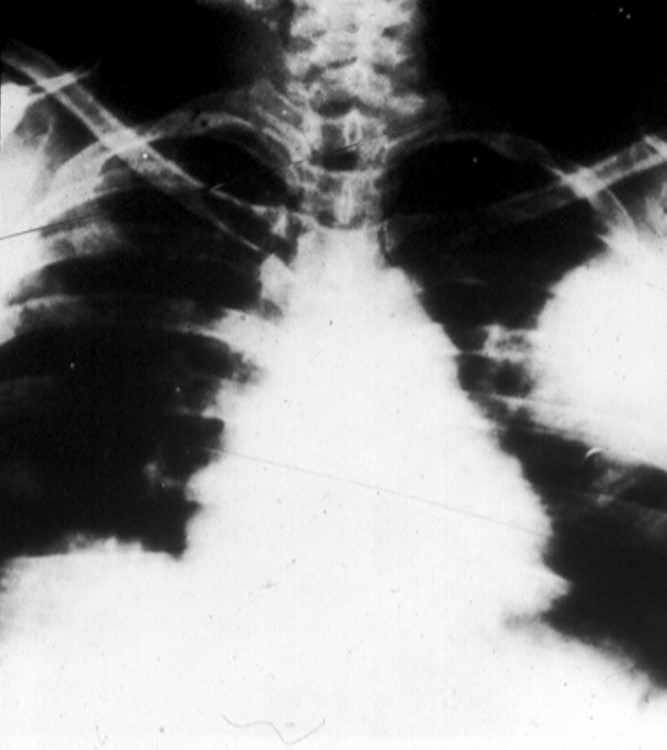

and inspiratory crackles. You obtain a chest x-ray (Panel A) and collect a sputum

Panel A. The patient's chest x-ray

The x-ray shows a large area of consolidation in the left mid-lung field and early apical cavitation in the right lung. There is evidence of mediastinal widening due to lymphatic spread of Y. pestis.